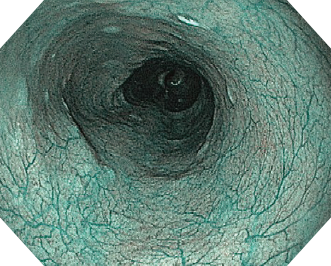

遠景も明るく、近接画像にもハイビジョン画質ならではの解像力で、繊細な粘膜構造の視認性も向上しました。

EVIS EXERAⅢ×GIF-H190N 症例画像